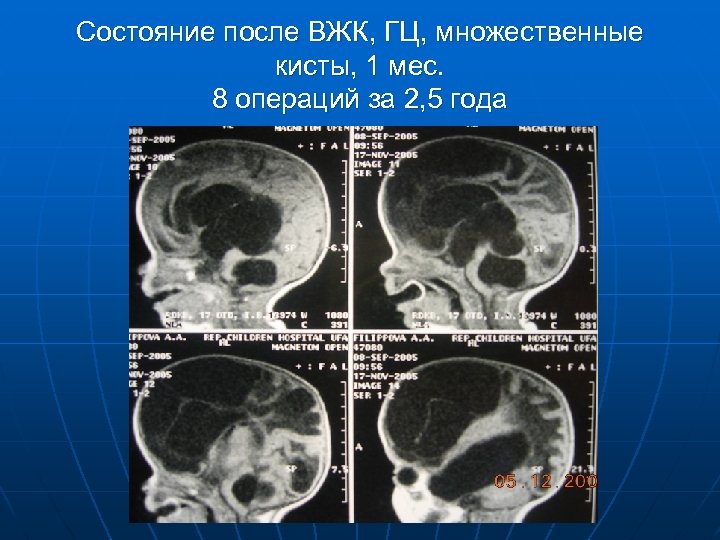

Состояние после ВЖК, ГЦ, множественные кисты, 1 мес. 8 операций за 2, 5 года